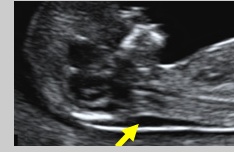

Translucenza NucaleLa translucenza nucale (NT) è la manifestazione ecografica dell’accumulo sottocutaneo di fluido dietro il collo fetale nel primo trimestre di gravidanza.

L’epoca gestazionale ottimale per la misurazione della NT è 11+0-13+6 settimane. La lunghezza vertice-sacro minima deve essere di 45 mm. e quella massima di 84 mm.

Nei feti euploidi la NT aumenta col crescere della lunghezza vertice-sacro.

Translucenza NucalePer una determinata lunghezza vertice-sacro, ogni misurazione di NT rappresenta un coefficiente di probabilità che viene moltiplicato per il rischio a priori basato sull’età materna e l’epoca gestazionale con lo scopo di calcolare un nuovo rischio. Maggiore è la misurazione della NT e, di conseguenza, il suo coefficiente di probabilità, più alto sarà il nuovo rischio.